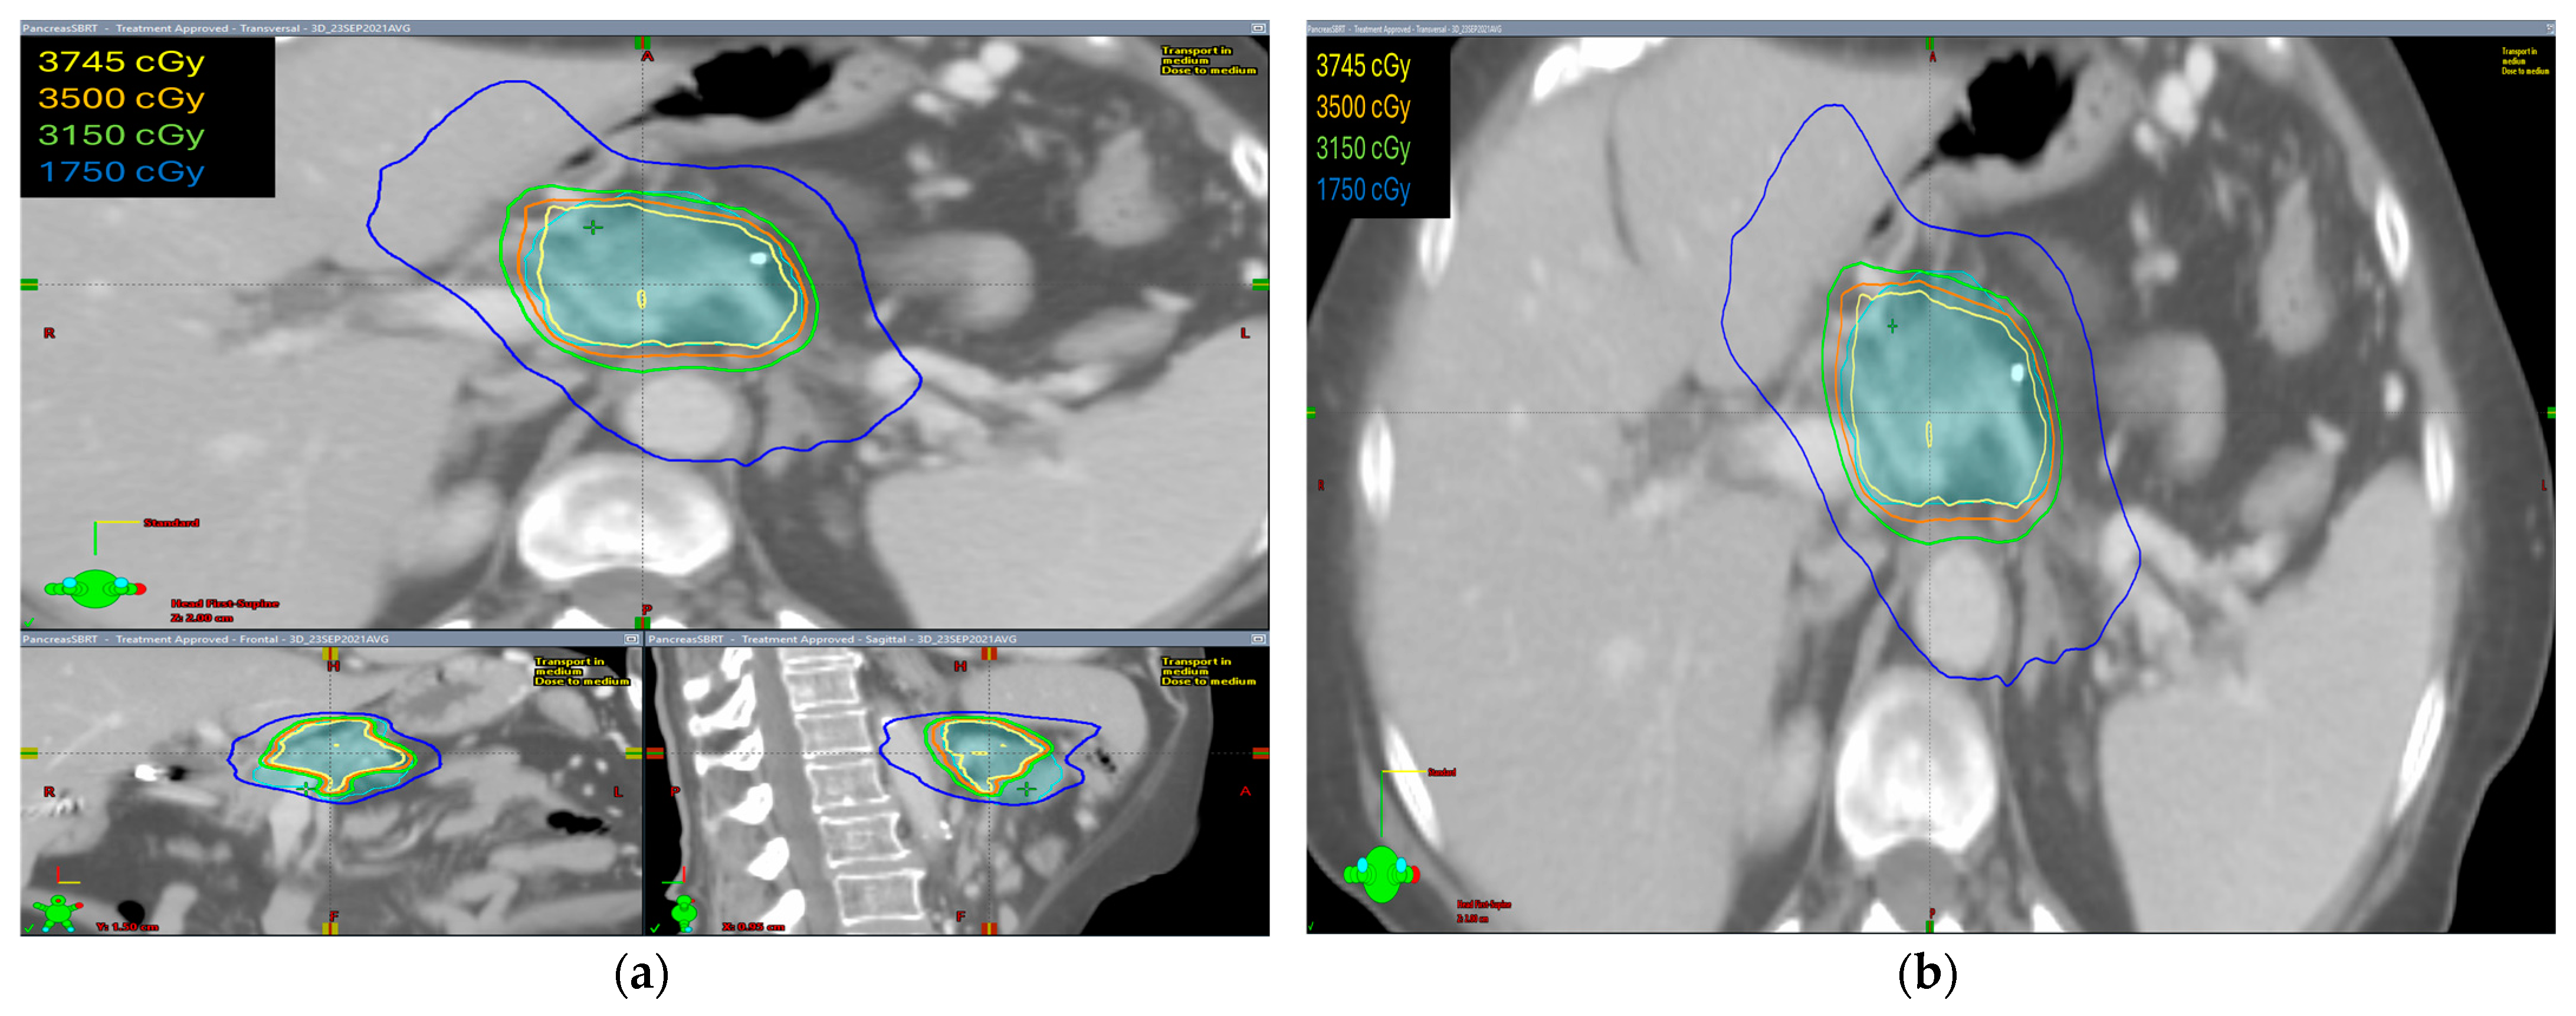

The radiation prescription dose was 35 Gy in five fractions in ten patients (58.8%). In five patients, the dose prescription was reduced to 30–33 Gy in five fractions and two patients received 40–50 Gy in five fractions. Median GTV volume was 28.60 cc (range 4.9–145.8 cc), median ITV was 29.15 cc (range 5.0–149.7 cc), and median PTV was 75.1 cc (range 19.9–255.3 cc). The isodose distribution for both abdominal compression and breath-hold technique is shown in Figure 1 and Figure 2, respectively.

The isodose distribution curves for target coverage and normal tissue dosing were evaluated. We found that the ITV was generated only in patients with abdominal compression to encompass the internal organ motion during treatment. Hence, PTV volumes were larger in these patients as compared with patients treated with breath-hold in which no ITV was drawn and smaller PTV volumes were irradiated.

Figure 1. The isodose distribution using abdominal compression technique (a) axial, coronal, and sagittal views (b) axial view.